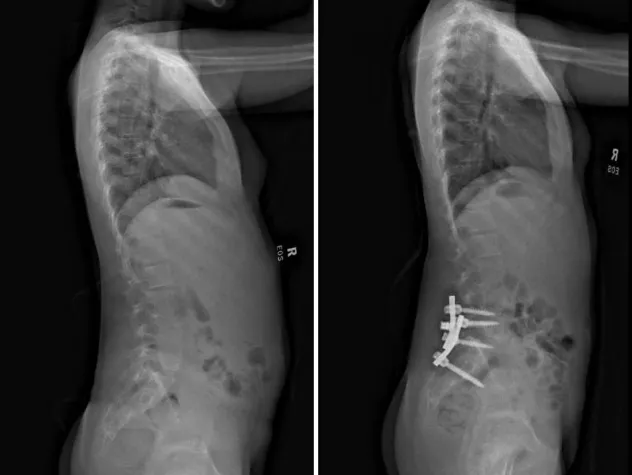

Our pediatric orthopedic specialists from Columbia are among the top in the country, offering specialized expertise in surgical and non-surgical treatments. Renowned for their expertise in congenital, neuromuscular, and traumatic disorders, clinicians and surgeons at the Children's Hospital of New York are also seasoned researchers, seeking to make surgeries safer while optimizing functional and mobility outcomes.

Pediatric Orthopedics